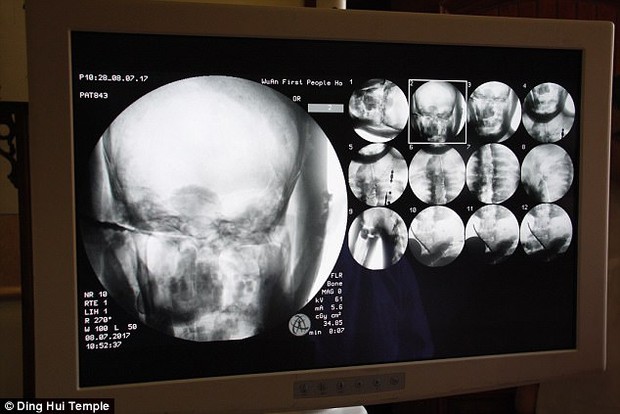

Theo tờ Daily Mail, đầu tháng 7 năm 2017, các nhà khoa đã tiến hành chụp CT để "nhìn thấu" bên trong xác ướp mạ vàng của nhà sư Ci Xian nổi tiếng Trung Quốc. Nhà sư Ci Xian được cho là một nhà sư được vạn dân kính trọng, ông đã đi từ Ấn Độ cổ đại đến Trung Quốc cổ đại để quảng bá Phật giáo.

Ngày 8/7/2017, trước sự chứng kiến của các nhà sư, giới truyền thông và nhiều người dân, các nhà khoa học đã tiến hành chụp CT xác ướp nhà sư Ci Xian.

Ban quản lý của ngôi chùa đã sắp xếp một buổi chụp CT xác ướp nhà sư Ci Xian vào ngày 8 tháng 7 năm 2017

Mọi người đều bàng hoàng khi các bác sĩ cho biết nhà sư Ci Xian vẫn còn nguyên bộ xương, và một bộ não hoàn chỉnh. Tức xác ướp này đã được bảo quản gần như nguyên vẹn sau hơn 1.000 năm. Điều này khiến giới khoa học sửng sốt với kỹ thuật ướp xác thời bấy giờ.

Bác sĩ Wu Yongqing nói với kênh Pear Video sau khi tiến hành chụp CT cho xác ướp: "Chúng tôi có thể thấy xương của ngài ấy khỏe mạnh như một người bình thường. Hàm trên, răng trên, xương sườn, xương sống và tất cả các khớp đều vẫn nguyên vẹn. Thật không thể tin được khi thấy điều này".